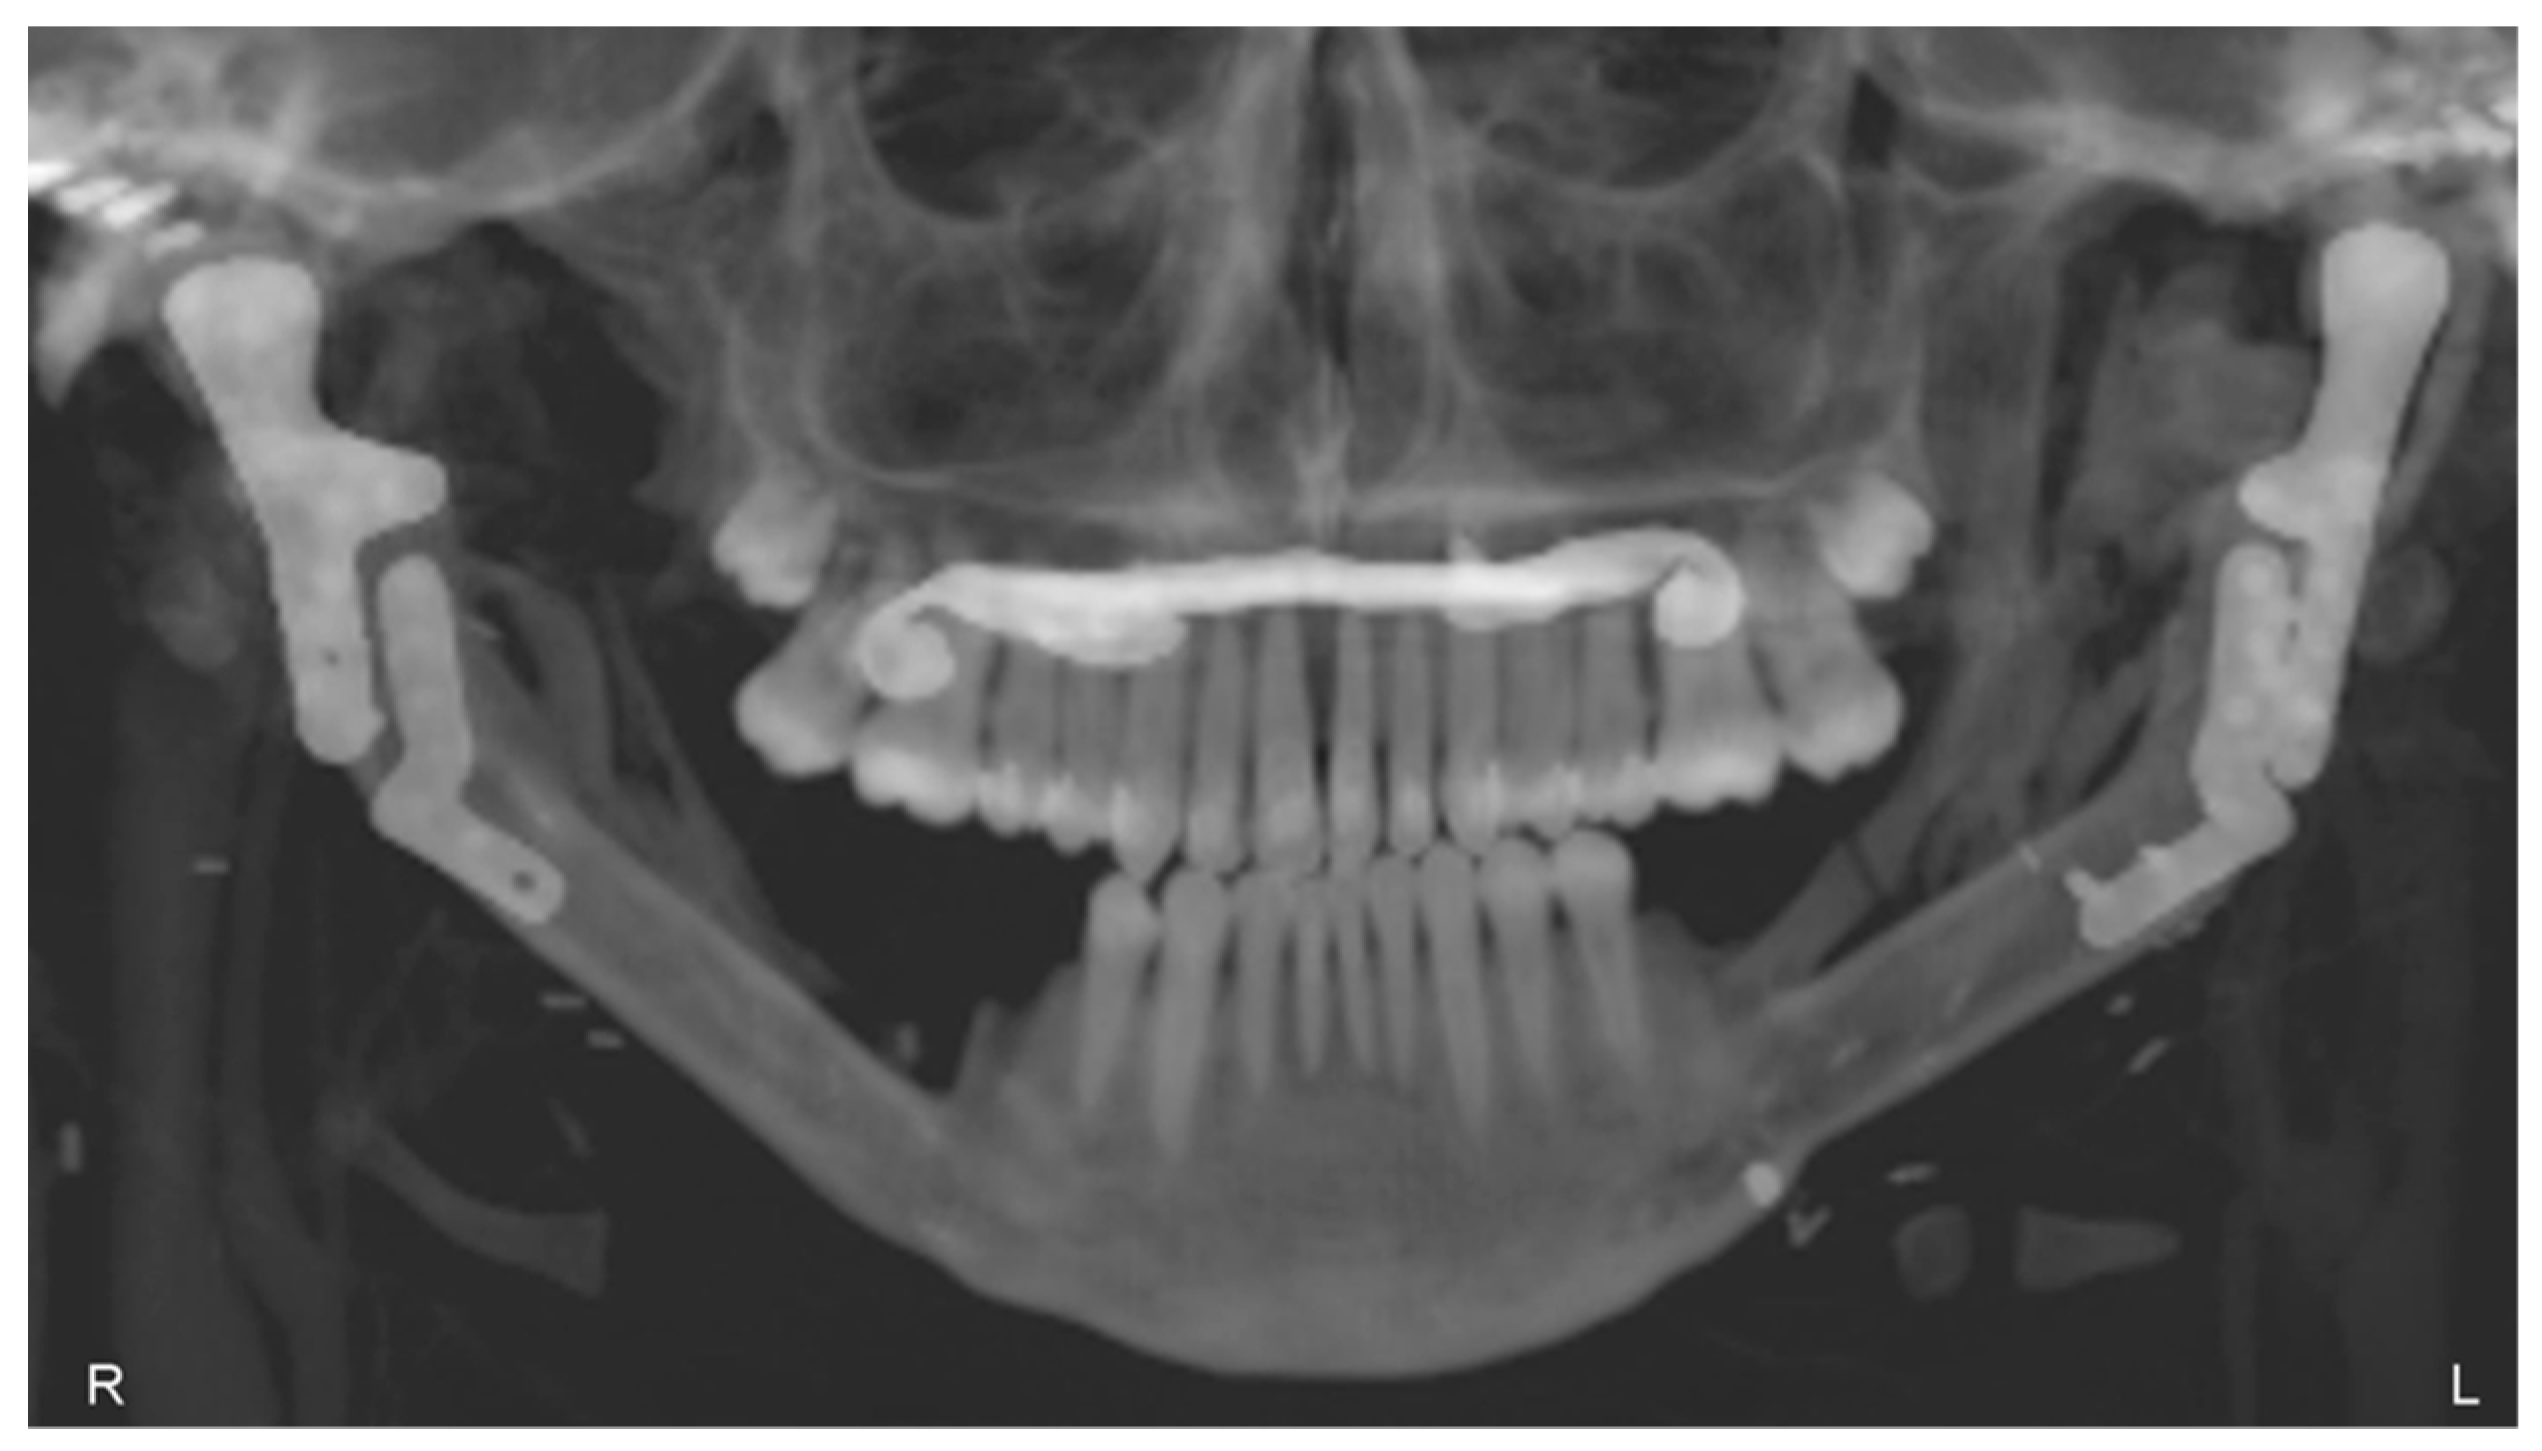

3.3. Postoperative Evaluation of Patient